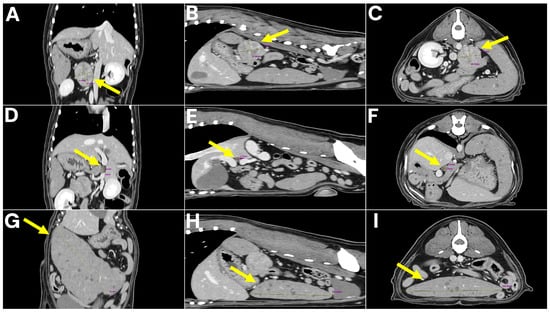

Long-Term Survival in a Dog After Adrenalectomy and Splenectomy for Two Different Malignancies with Portal Vein Involvement

Concurrent occurrence of two independent primary malignancies in a single dog is rare and presents diagnostic and surgical challenges. A 9-year-old neutered male Cocker Spaniel was diagnosed with adrenal pheochromocytoma and splenic diffuse large B-cell lymphoma. Abdominal imaging revealed two distinct masses. Surgical [...] Read more.

Concurrent occurrence of two independent primary malignancies in a single dog is rare and presents diagnostic and surgical challenges. A 9-year-old neutered male Cocker Spaniel was diagnosed with adrenal pheochromocytoma and splenic diffuse large B-cell lymphoma. Abdominal imaging revealed two distinct masses. Surgical management included adrenalectomy, splenectomy, mesenteric lymphadenectomy, and excision of a small mass adherent to the portal vein adventitia. Histopathology confirmed two separate malignancies, with chromogranin A positivity supporting pheochromocytoma and CD20 positivity confirming B-cell lymphoma. No additional metastatic lesions were identified, and the portal vein-associated mass was considered an isolated lesion closely adherent to the vessel wall, with its exact pathogenesis remaining uncertain. To the authors’ knowledge, this represents the first veterinary report describing adrenal pheochromocytoma with portal vein involvement successfully managed by surgical removal. The patient recovered well and remained disease-free for three years without adjuvant therapy. This case emphasizes that, even in technically demanding situations, meticulous surgical planning and comprehensive oncologic assessment can achieve durable remission and inform future approaches to complex veterinary cancers. Full article